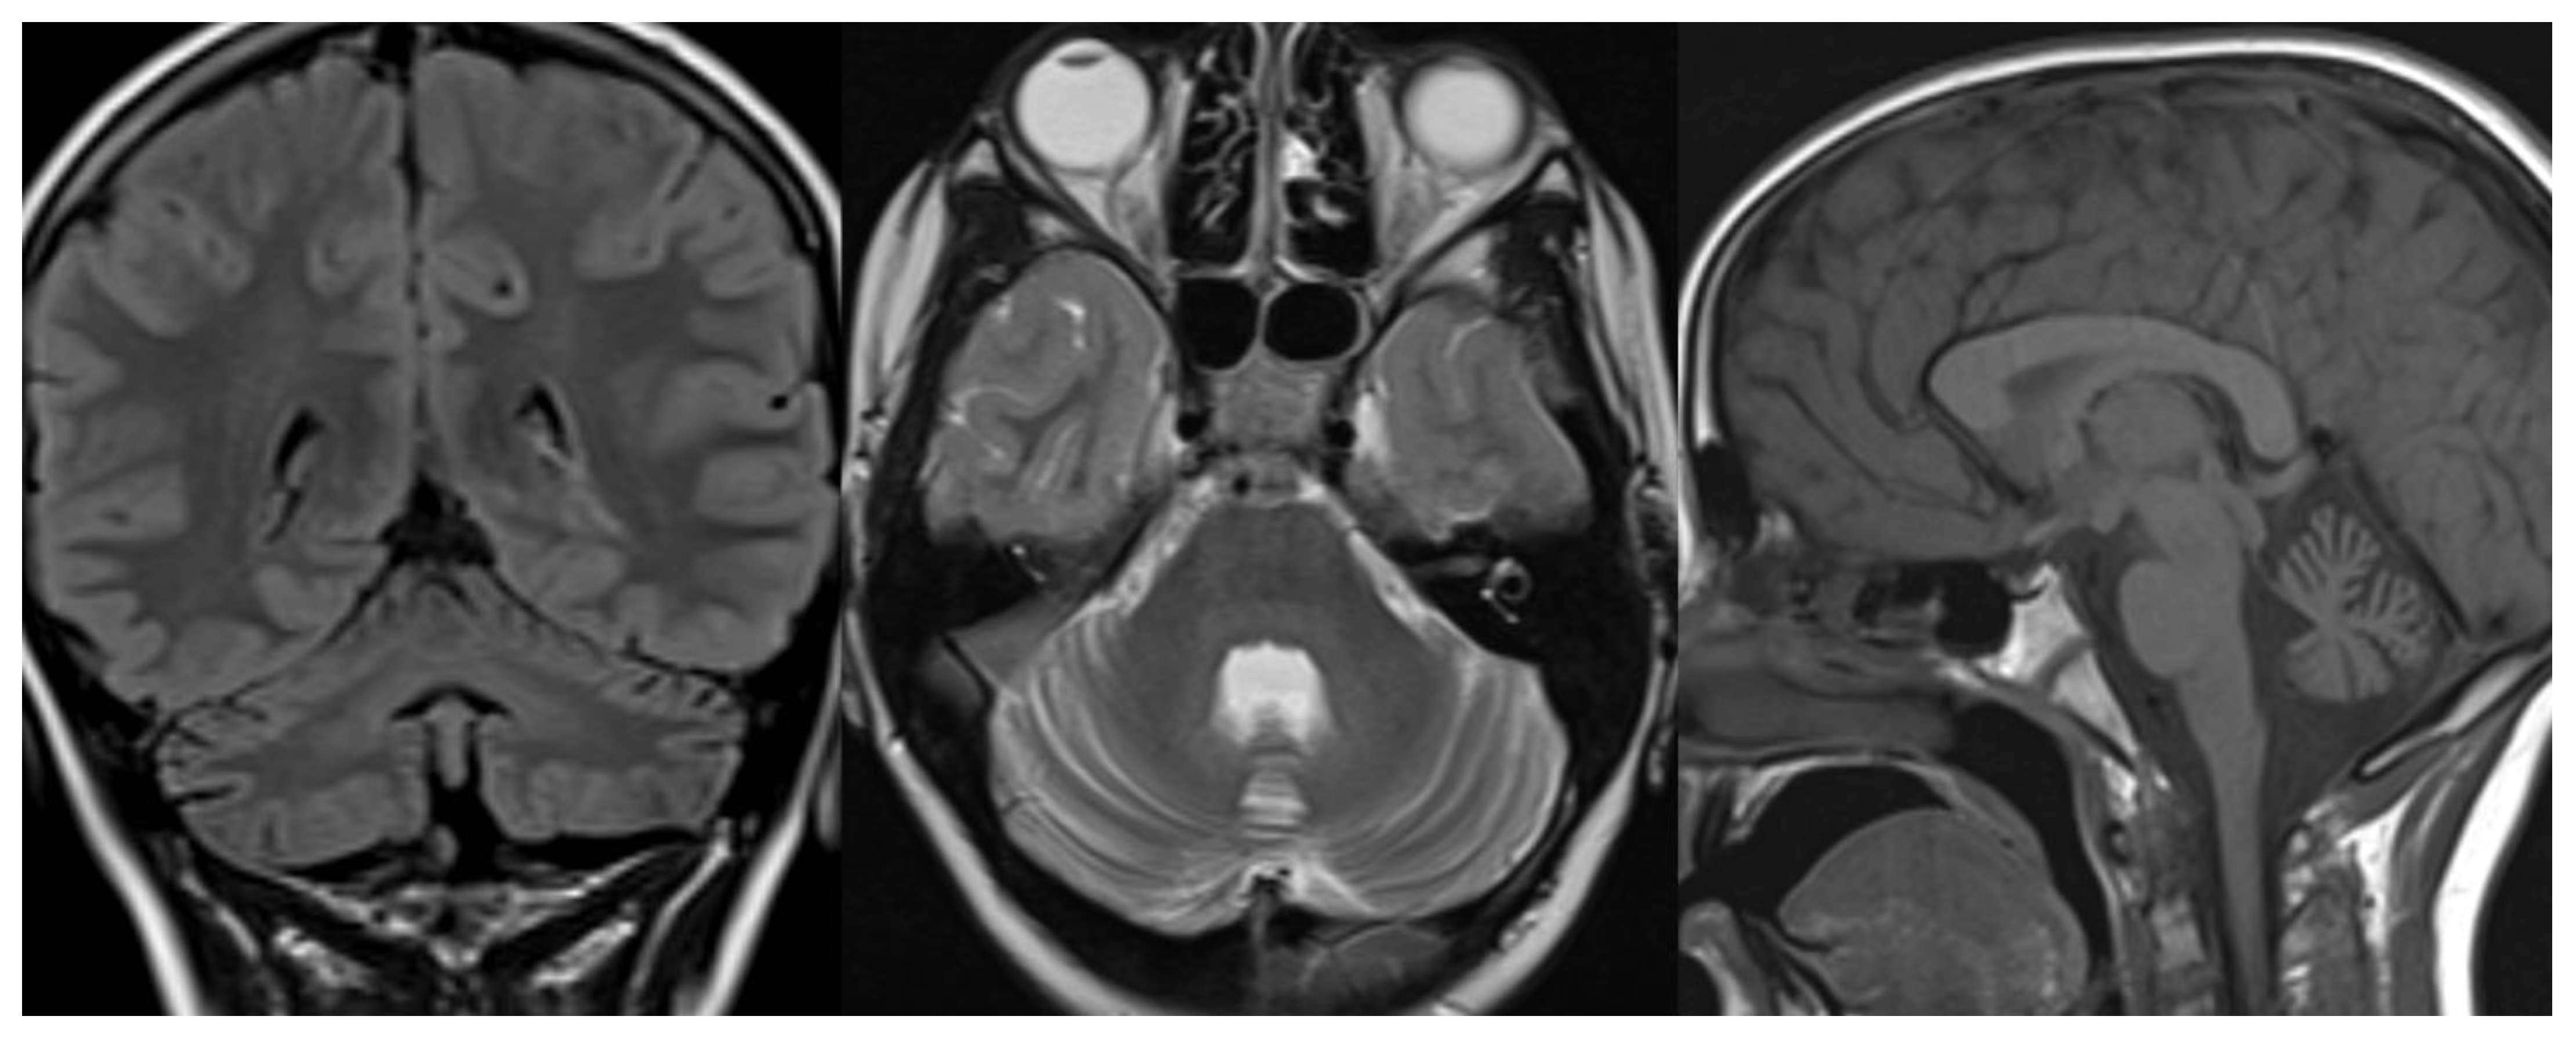

Radiological imaging is limited to MRI since CT and studies with x-rays can increase the risk of genetic mutation in these patients highly sensitive to DNA damage by ionizing radiation [37,38]. MR images reveal diffuse cerebellar atrophy, with initial involvement of the superior vermis and lateral cerebellar hemispheres and unusual decreased cortical thickness along cerebellar hemispheres. Supratentorial brain shows no sign of volume loss. At the same time, confluent hyperintensities in T2/FLAIR and multiple focal hypointensities (thought to be deposits of haemosiderin related to capillary telangiectasia) are seen in deep white matter, mainly in adult patients [39]. Hypoplasia of the inferior vermis and a large cisterna magna were also frequent signs [40] (Figure 7).

Figure 7.

Ataxia telangiectasia (AT). Brain MRI scan of a 10-year-old girl. MR images reveal severe atrophy of the cerebellar hemispheres, decreased thickness of the cortex of superior cerebellar hemispheres, and hypoplasia of inferior vermis.